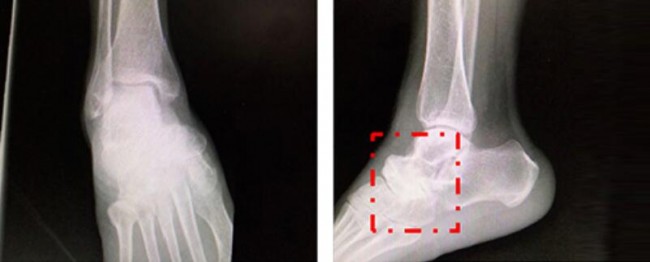

经怀集县人民医院进行X线片、CT、MR等传统影像检查,初步诊断为:1.右足舟骨坏死。2.右距舟关节骨关节炎。3.右跟骰关节骨关节炎。拟行右距舟关节、跟骰关节融合术。

图片来源:丁焕文教授团队

丁焕文教授团队结合患者症状、体征临床诊断为Muller-Weiss病。通过3D精准定位确认患者病变部位为附横关节。通过会诊讨论,决定为患者实行“足内侧柱延长、距舟关节融合、距骨骰骨融合固定”手术。